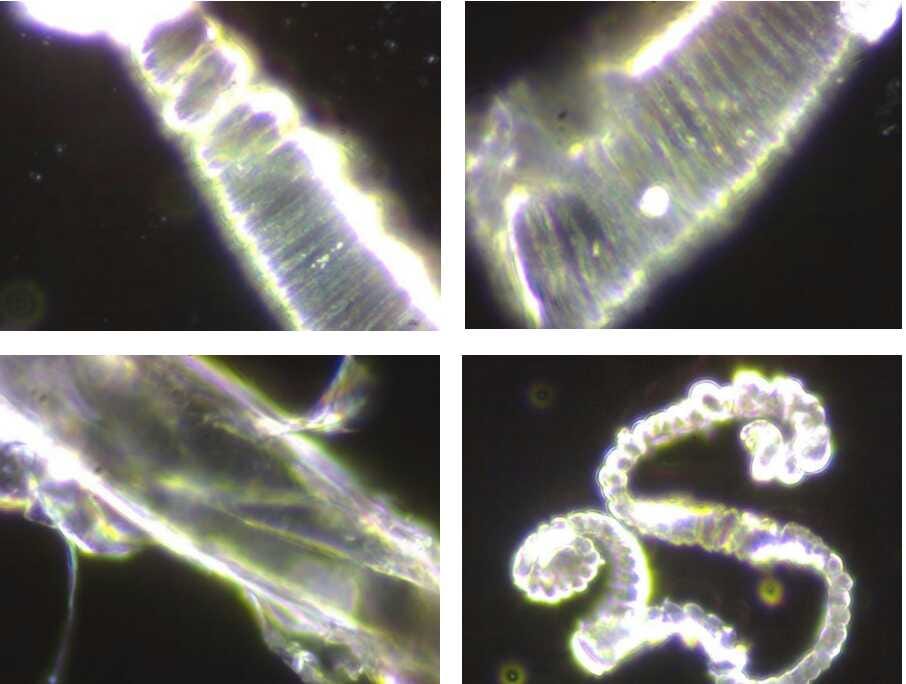

Estas 4 imágenes ilustran la variedad de fenómenos y objetos inusuales encontrados en la sangre de sujetos vacunados con Comirnaty BioNTech/Pfizer (Cortesía de Helen Krenn)MÁS

These substances, furthermore, “are visible under the dark-field microscope as distinctive and complex structures of different sizes, can only partially be explained as a result of crystallization or decomposition processes, [and] cannot be explained as contamination from the manufacturing process,” the researchers found.